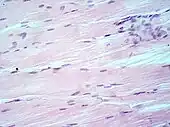

Lung tissue taken from an emphysema patient. Cell nuclei (blue-purple), red blood cells (bright red), other cell bodies and extracellular material (pink), and air spaces (white).- Muscle tissue, cell nuclei (blue-purple), cell body (pink).

H&E is the combination of two histological stains: hematoxylin and eosin. The hematoxylin stains cell nuclei a purplish blue, and eosin stains the extracellular matrix and cytoplasm pink, with other structures taking on different shades, hues, and combinations of these colors.[5][6] Hence a pathologist can easily differentiate between the nuclear and cytoplasmic parts of a cell, and additionally, the overall patterns of coloration from the stain show the general layout and distribution of cells and provides a general overview of a tissue sample's structure.[7] Thus, pattern recognition, both by expert humans themselves and by software that aids those experts (in digital pathology), provides histologic information.

Hematoxylin principally colors the nuclei of cells blue or dark-purple,[6][15][14] along with a few other tissues, such as keratohyalin granules and calcified material. Eosin stains the cytoplasm and some other structures including extracellular matrix such as collagen[5][7][14] in up to five shades of pink.[8] The eosinophilic (substances that are stained by eosin)[5] structures are generally composed of intracellular or extracellular proteins. The Lewy bodies and Mallory bodies are examples of eosinophilic structures. Most of the cytoplasm is eosinophilic and is rendered pink.[10][15] Red blood cells are stained intensely red.